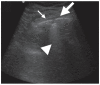

Results: We included 17 studies, reporting a total of 274 patients with M. pneumoniae, 30 with fungal infection and 213 with pulmonary tuberculosis (TB). Most of the studies on M. pneumoniae in children found a specific LUS pattern, mainly consolidated areas associated with diffuse B lines. The typical LUS pattern in TB consisted of consolidation and small subpleural nodes. Only one study on fungal disease reported LUS specific patterns (e.g., indicating "halo sign" or "reverse halo sign").